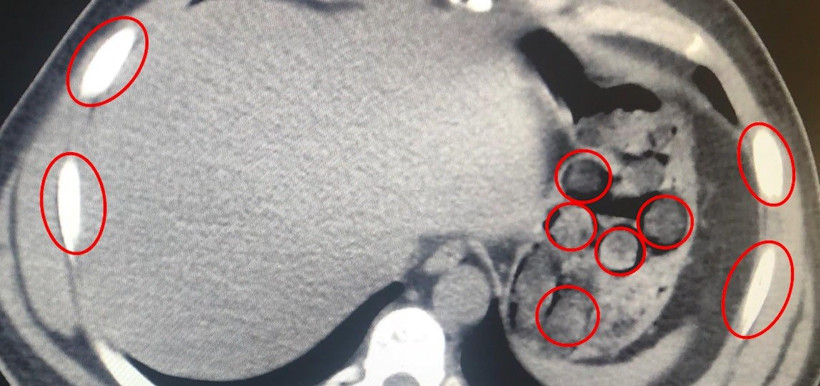

Düzenlenen narkotik operasyonunda yabancı uyruklu iki şüpheli, midelerinde taşıdıkları 136 uyuşturucu kapsülleriyle yakalandı.

Bitlis İl Emniyet Müdürlüğü Narkotik Suçlarla Mücadele Şube Müdürlüğü ekipleri, uyuşturucu ile mücadele kapsamında önemli bir operasyona imza attı. Tatvan ilçesinde durdurulan bir otobüste yolcu olarak seyahat eden yabancı uyruklu 2 kişi gözaltına alındı. Şahısların yapılan tıbbi müdahalesinde, yuttukları 136 kapsül halinde toplam 1 kilo 48 gram metamfetamin ele geçirildi. Uyuşturucu Madde İmal ve Ticareti suçundan gözaltına alınan zanlılar, çıkarıldıkları adli mercilerce tutuklanarak cezaevine gönderildi. Emniyet yetkilileri, vatandaşların huzur ve güvenliği için uyuşturucu madde imalatı, kaçakçılığı ve kullanımına karşı mücadelenin kararlılıkla sürdürüleceğini vurguladı.